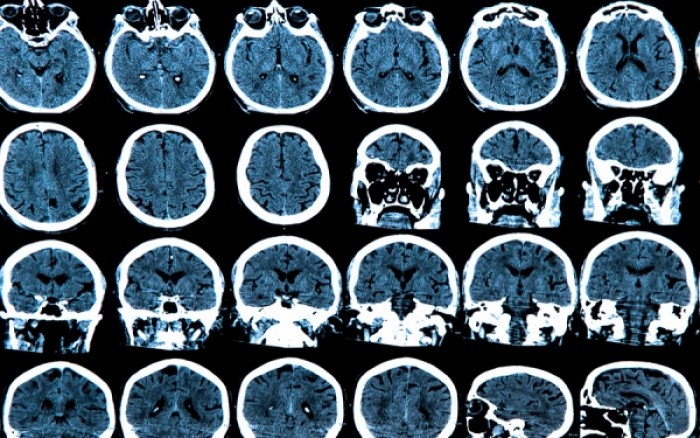

Νέοι δρόμοι ενδέχεται να ανοίξουν στον τομέα της έρευνας για τον εξαιρετικά επικίνδυνο καρκίνο στο κεφάλι εάν δοκιμαστούν φάρμακα που μέχρι τώρα εξυπηρετούσαν άλλους σκοπούς. Σύμφωνα με το βετεράνο ερευνητή Geoff Pilkington, φάρμακα που χρησιμοποιούνται για άλλες παθήσεις μπορούν να αποδειχθούν αποτελεσματικά στην αντιμετώπιση του καρκίνου στο κεφάλι. Ορισμένα αντικαταθλιπτικά φαίνεται πως μπορούν να αποδειχθούν εξαιρετικά αποτελεσματικά στην περίπτωση αυτή. Οι δραστικές των αντικαταθλιπτικών περνούν τον αιματο-εγκεφαλικό φραγμό, ο οποίος εμποδίζει επικίνδυνες τοξίνες να φτάσουν στον εγκέφαλο. Ο Δρ Pilkington μελετά μια κλάση φαρμάκων που ονομάζονται τρικυκλικά αντικαταθλιπτικά από...